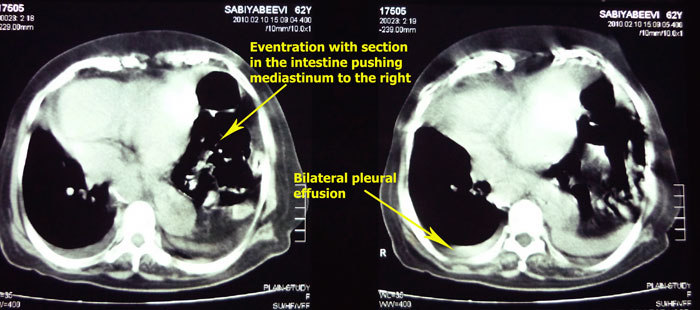

-A patient

presented with acute dyspnea.

-Patient was investigated and found to have eventration of diaphragm and

taken up for surgery for correction by cardiothoracic surgeon.

-Summary of radiological findings:

-Eventration of left hemidiaphragm with mediastinal & tracheal shift to

the right.

-Cardiomegaly with bilateral pleuarl effusion.

-Calcified lesion anterior and to left of trachea in the superior

mediastinum

(? calcified thyroid nodule, ? calcified lymph node)